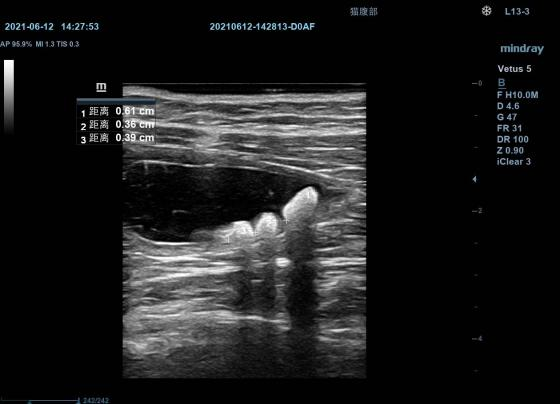

超声检查之——B超

B超可不能仅仅字面理解为孕检

也可用于体检和诊断评估腹部里面的其它器官(脾脏 淋巴结 胃肠  膀胱等)

肚子里是否是腹水、膀胱是否有结石等

膀胱结石超声影像▲